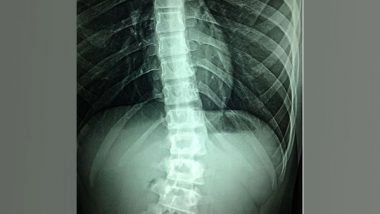

Washington [US], September 21 (ANI): Currently, there are no effective treatments for spinal cord injury; physical rehabilitation can help patients regain some mobility, but the outcomes are severely limited in severe cases due to the failure of spinal neurons to regenerate naturally after injury.

Researchers led by Simone Di Giovanni at Imperial College London in the UK show that weekly treatments with an epigenetic activator can aid the regrowth of sensory and motor neurons in the spinal cord when given to mice 12 weeks after severe injury.

Building on their past success, researchers used a small molecule called TTK21 to activate genetic programming that induces axon regeneration in neurons. TTK21 changes the epigenetic state of genes by activating the CBP/p300 family of co-activator proteins. They tested TTK21 treatment in a mouse model of severe spinal cord injury. The mice lived in an enriched environment that gave them opportunities to be physically active, as is encouraged in human patients.

Treatment began 12 weeks after severe spinal cord injury and lasted for 10 weeks. Researchers found several improvements after TTK21 treatment compared with control treatment. The most noticeable effect was more axon sprouting in the spinal cord. They also found that retraction of motor axons above the point of injury halted, and that sensory axon growth increased. These changes were likely due to the observed increase in gene expression related to regeneration. The next step will be to enhance these effects even more and to trigger the regenerating axons to reconnect to the rest of the nervous system so that animals can regain their ability to move with ease.

Di Giovanni adds, "This work shows that a drug called TTK21 that is administered systemically once/week after a chronic spinal cord injury (SCI) in animals can promote neuronal regrowth and an increase in synapses that are needed for neuronal transmission. This is important because chronic spinal cord injury is a condition without a cure where neuronal regrowth and repair fail. We are now exploring the combination of this drug with strategies that bridge the spinal cord gap such as biomaterials as possible avenues to improve disability in SCI patients." (ANI)